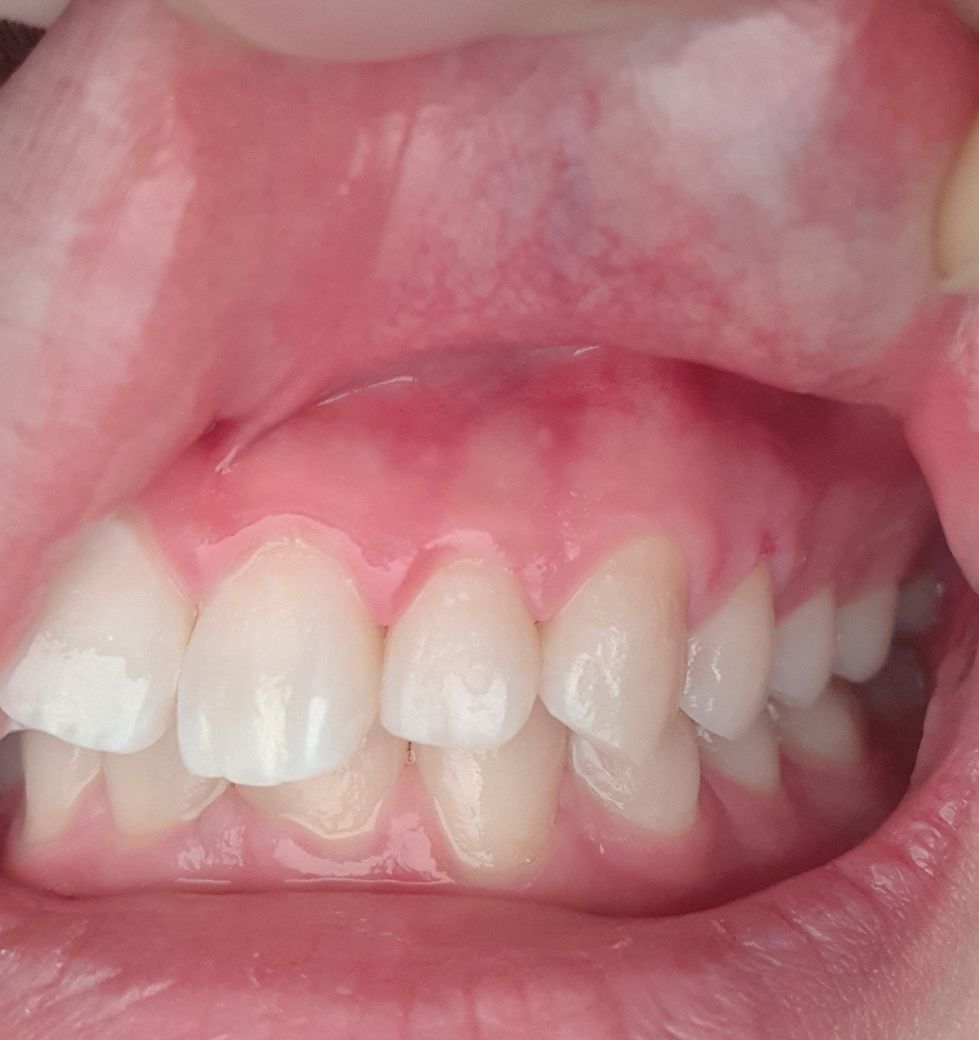

하루 뒤 양치하는데 윗 잇몸 앞니에서 오른쪽 두번째 위가

아프더라구요 혀로 만지면 뭔가 살짝 묘하게 튀어나온 느낌?

왼쪽위 작은어금니 쪽에 살짝 상처가 잇는거 같습니다. 그쪽부위에 염증이 잇어서 스켈링을 쫌 강하게 하신거 같네요. 크게 문제가 잇거나 그렇진 않습니다.

사진 상으로는 건강한 잇몸으로 보이기 때문에 일시적인 증상으로 생각되며 증상이 계속되면 해당 치과선생님께 여쭤보세요